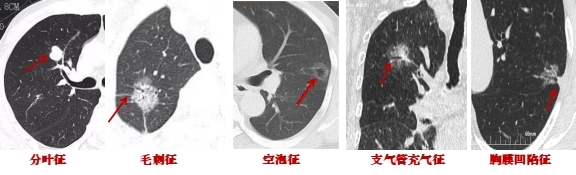

1.結(jié)節(jié)的形態(tài)變化:肺結(jié)節(jié)持續(xù)存在且逐漸增大、密度逐漸增高,惡變可能性大,短期內(nèi)結(jié)節(jié)大小急劇變化的多為良性。若結(jié)節(jié)8mm~15mm,有分葉、毛刺、胸膜牽拉、含氣細(xì)支氣管征和小泡征、偏心厚壁空洞這些CT惡性征象,大概率是惡性的。